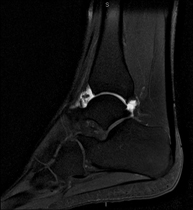

Exploració per estudiar aquesta articulació i les lesions freqüents de lligaments (esquinços), així com l'afectació d'altres estructures, com el cartílag o l'os. També és de gran utilitat per diagnosticar alteracions al tendó d'Aquil·les (tendinitis o trencaments). La durada aproximada és de 20 minuts. No utilitza radiació ionitzant. - RM de Peu

- Artro-RM Tobillo

Exploración para el estudio de las lesiones en pequeñas estructuras anatómicas de la articulación que suelen lesionarse en pacientes que sufren luxación o inestabilidad crónica. El estudio viene precedido por una inyección de contraste en el interior de la articulación, realizada bajo control de rayos X. Duración global de los dos procedimientos es de 50 minutos.